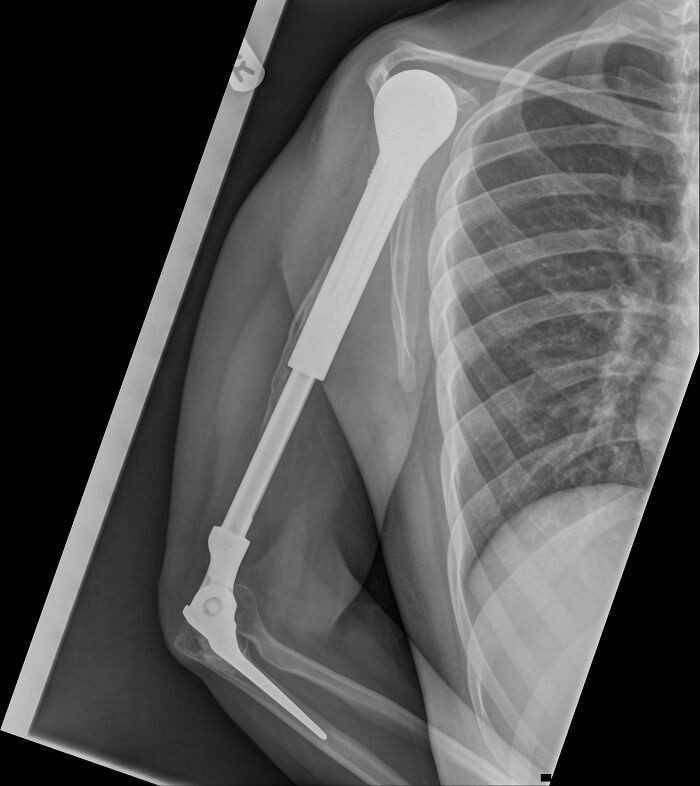

«Вот рентгеновский снимок моей металлической руки»